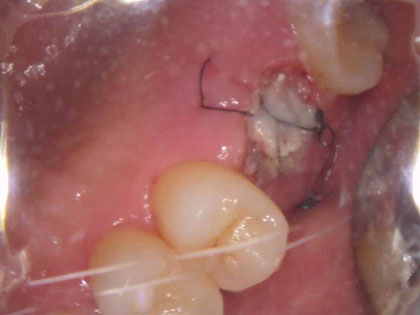

• 治療中の写真がこちら

• インプラント治療中1

• インプラント治療中2

• インプラント治療中3

• インプラント治療中4